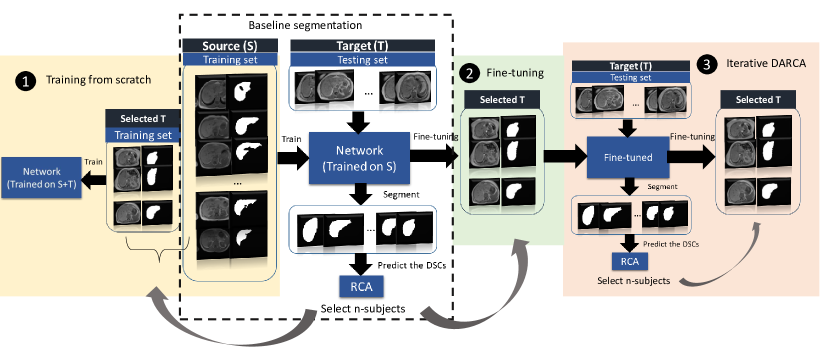

We present results for using different strategies to investigate the effect of RCA-based subject selection for domain adaptation, as shown in Figure 2. We use 3-fold cross-validation with the same random splits in all experiments. As the baseline, we trained the network with all S data and tested it to segment the T images. We predict the DSCs of all target segmentations using RCA. After we sort their DSCs (lowest to highest confidence), we select -subjects from T domain to be included with their corresponding manual annotations in the training set mimicking an active learning approach.

Figure 2-1 shows that RCA selects -subjects from T domain, to be manually labeled and incorporated into training dataset. For this experiment, we compared best-/worst-5 subjects selected by RCA and the real best-/worst-5 (real DSCs from the target ground-truth). Besides, we also run random-5 subject selection (repeated with three different random combination and taking the average) to be trained from scratch.

In Figure 2-2, we fine-tune the pre-trained network (from S), with -subjects selected by RCA. Fine-tuning requires less time than training from scratch. Here, we fine-tune with three different selections (random, real DSC, and RCA) at different set size (2, 5, 10, 15, and all of the T data). Table 3 shows the results when we fine-tune using all of the T data which is very similar (DSC: 0.830) to when we train from scratch (DSC: 0.831).

3.3 Iterative DARCA

Different from the previous strategies, here, we wish to mimic the active learning domain adaptation [8], where at each iteration, RCA chooses -subjects from the target domain to fine-tune the baseline networks (see Figure 2-3). At the first iteration, we fine-tune the baseline network with best-5 subjects selected by RCA. This new network is used to segment the test images from target domain for which accuracy is again predicted using RCA. At the second iteration, we fine-tune the network again with the the best-5 and worst-5 selected subjects.